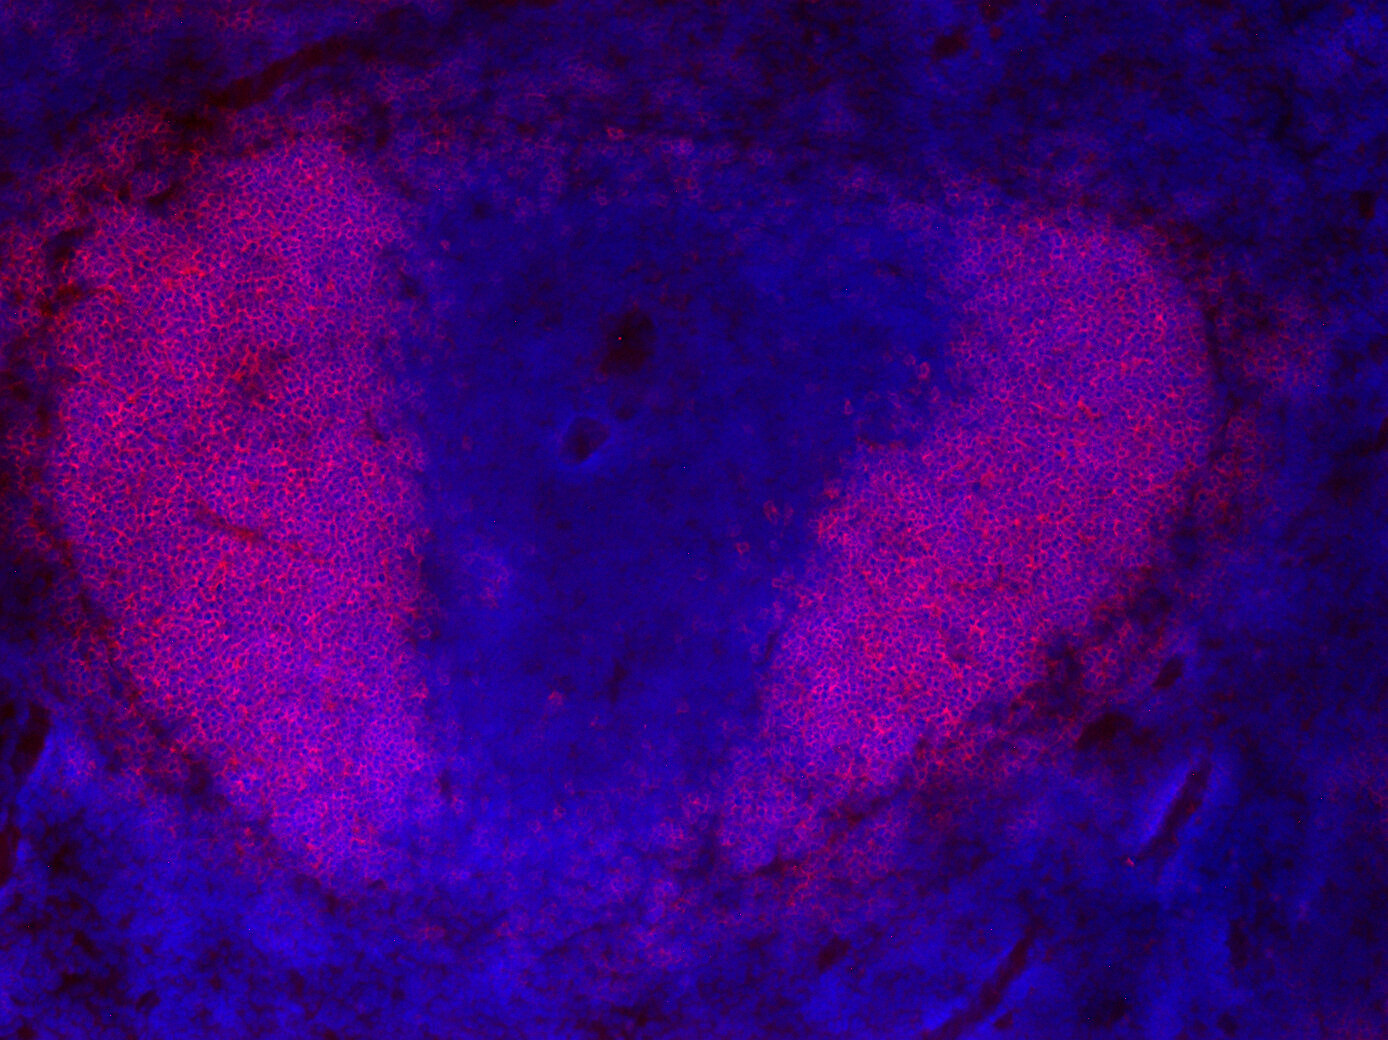

IHC: 1 : 200 gallery

IHC-Fr: 1 : 200 (see remarks) gallery

Chromogenic double staining for CD19 (DAB) and CD3e (RED) visualized T-cell and B-cell populations in the mouse spleen